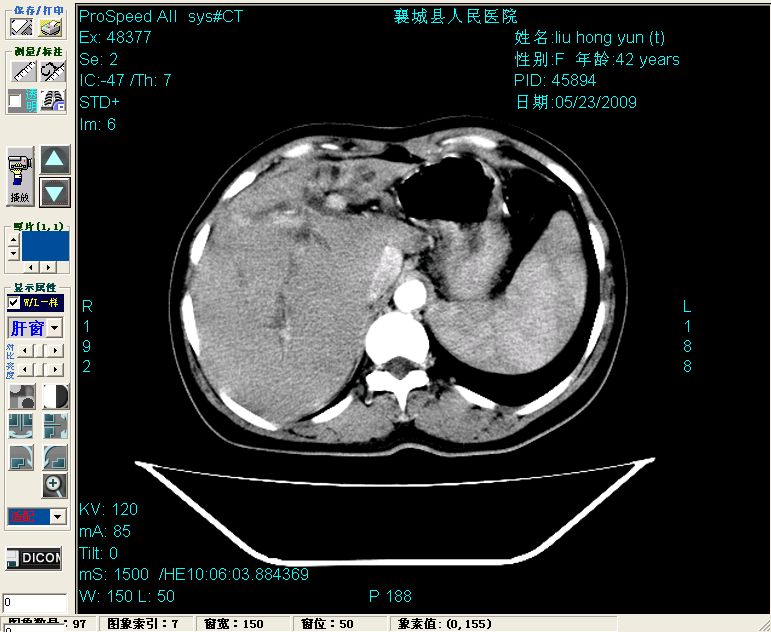

平扫:

增强:

平扫左肝外叶体积显著减小,左肝外叶见多房囊性低密度区,左肝实质及右肝前叶浅表实质呈低密度改变,左肝及右肝前叶胆管扩张,脾大

增强动脉期前述低密度区轻度早其强化,门脉期强化程度显著增高,延期扫描强化程度下降,但仍为相对高密度影

胰头部见结节状高密度影,其前方略可分辨扩强胆部管,平扫到增强始终有,但现在尚难与胃肠造影剂鉴别.

结合病史考虑,1现在引起黄疸体征的原因应该是胆总管胰段结石阻塞,建议局部胃肠造影剂排空后复查.

2左肝及右肝前叶表现考虑胆囊摘除术后所致的肝动门脉瘘形成,慢性纤维组织炎性增生.不完全除外左肝胆管细胞癌

3脾大,可能与动门脉瘘所致门脉高压有关